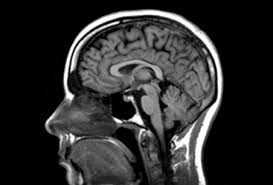

자기공명영상(MRI)

자기공명영상(MRI) 검사는 비침습적 성격과 뛰어난 영상 품질로 인해 현대 의학에서 빼놓을 수 없는 진단 수단이 되었습니다. 그러나 안전하고 효과적인 검사를 보장받기 위해서는 의료진의 지시에 따르고, 환자가 자신의 상태를 정확히 알고 있어야 합니다. 이로써 환자 진료에 있어서 정밀하고 세심한 접근이 가능해질 것입니다.